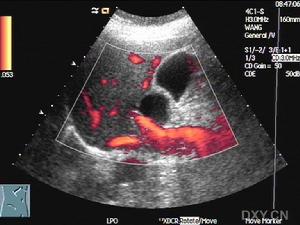

膽囊管綜合徵彩超圖片1.膽石症膽囊管內有小膽石的患者多方面的表現可酷似膽囊管綜合徵,包括臨床症狀、CCK刺激下的膽汁引流和膽囊造影。位於膽囊管中的小結石可在膽囊摘除術中或術後解剖被發現。